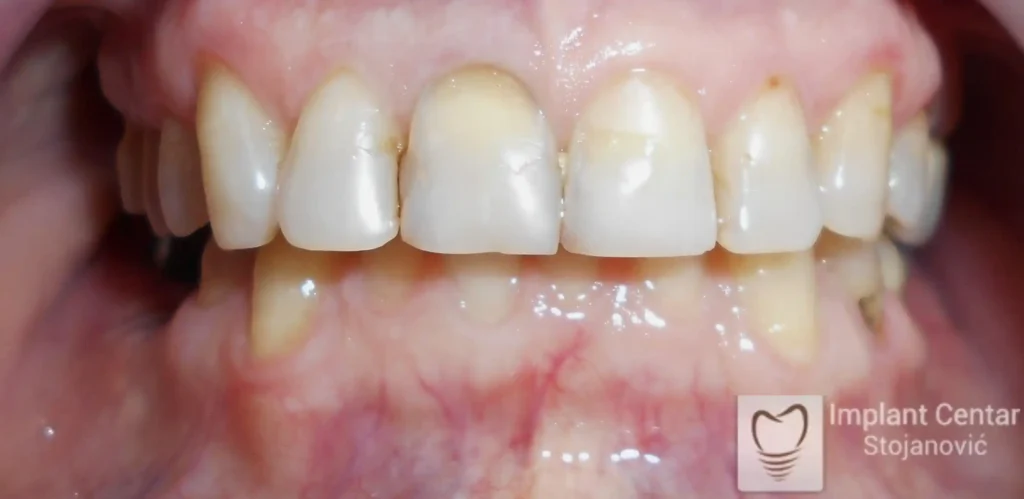

Tokom perioda oseointegracije, pacijent je bio zbrinut fiksnim privremenim krunicama, čime je već pet dana nakon intervencije obezbeđena potpuna funkcionalna i estetska rehabilitacija. Nakon završetka perioda integracije implantata, izrađeni su definitivni cirkonijum-keramički mostovi na implantatima.

Pacijent je izuzetno zadovoljan postignutim rezultatom, navodeći da po prvi put jasno oseća svoje nepce tokom žvakanja, kao i da se smeje sa punim samopouzdanjem.